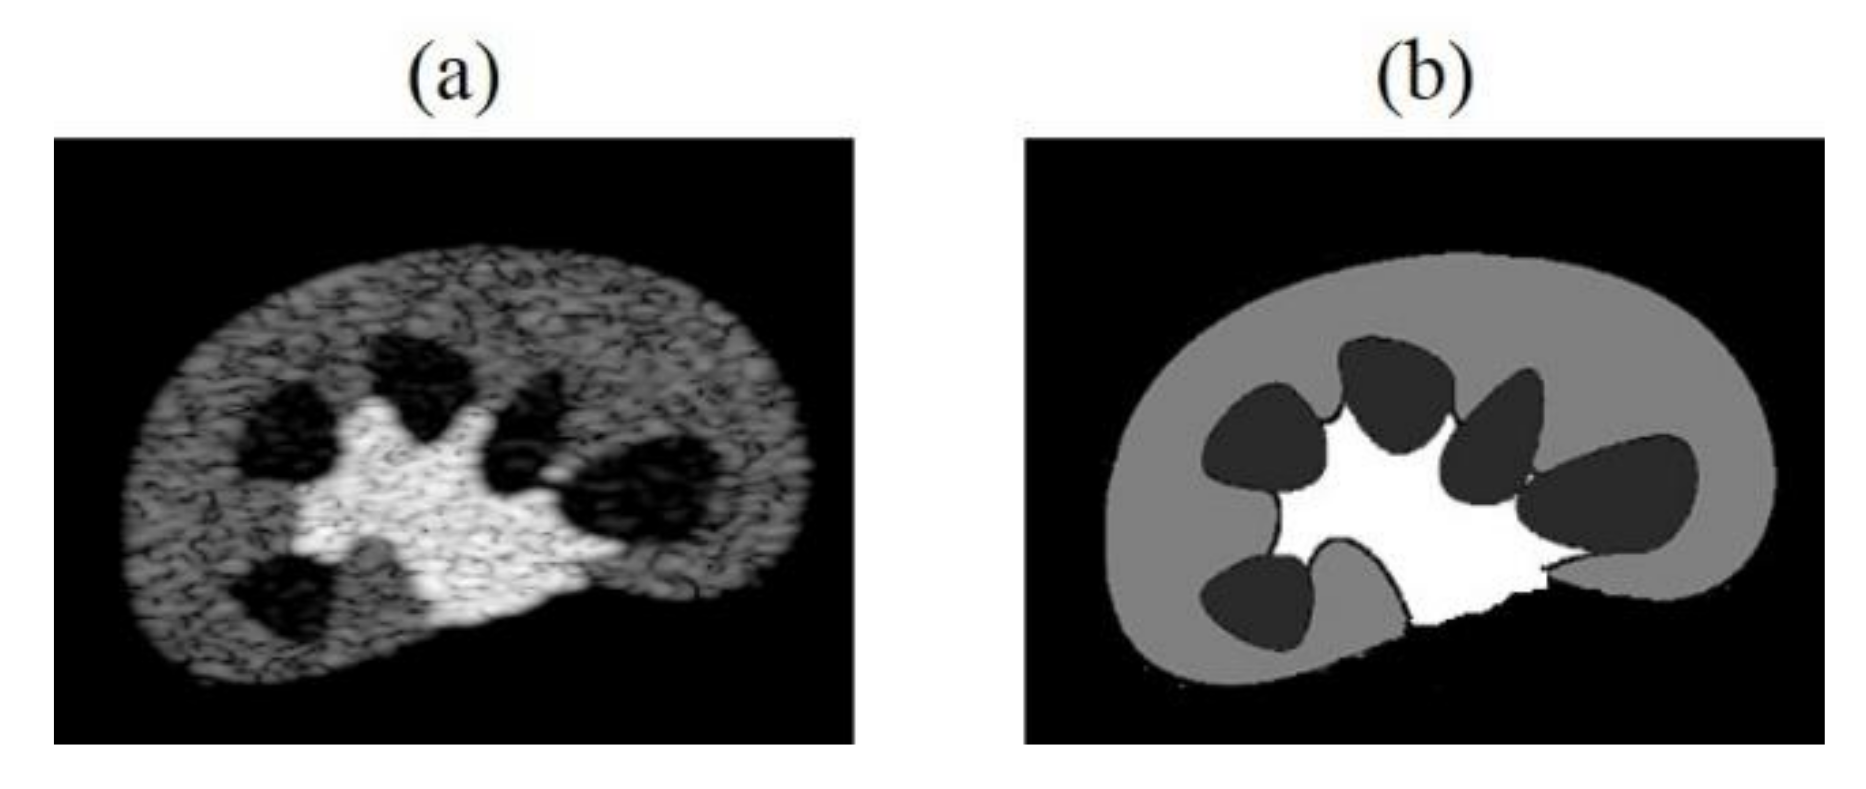

In the future, we can increase the number and diversity of training dataset. For example, by producing simulated training data which contains similar structures to in-vivo imaged tissue/organ as shown in Figure 13, or making datasets that simultaneously include simulated, phantom and clinical images, raising the overall generality of models. We can apply transfer learning to initialize the network weights of a new model through the trained CNN model, speed up training convergence and increase model stability. Besides, we can also increase the training times, and make subtle adjustments of loss functions and hyperparameters of the neural network to improve accuracy of the tissue echogenicity restoration and combine it with clinical applications.

Figure 13. (a) Kidney simulation B-mode image and (b) echogenicity map.